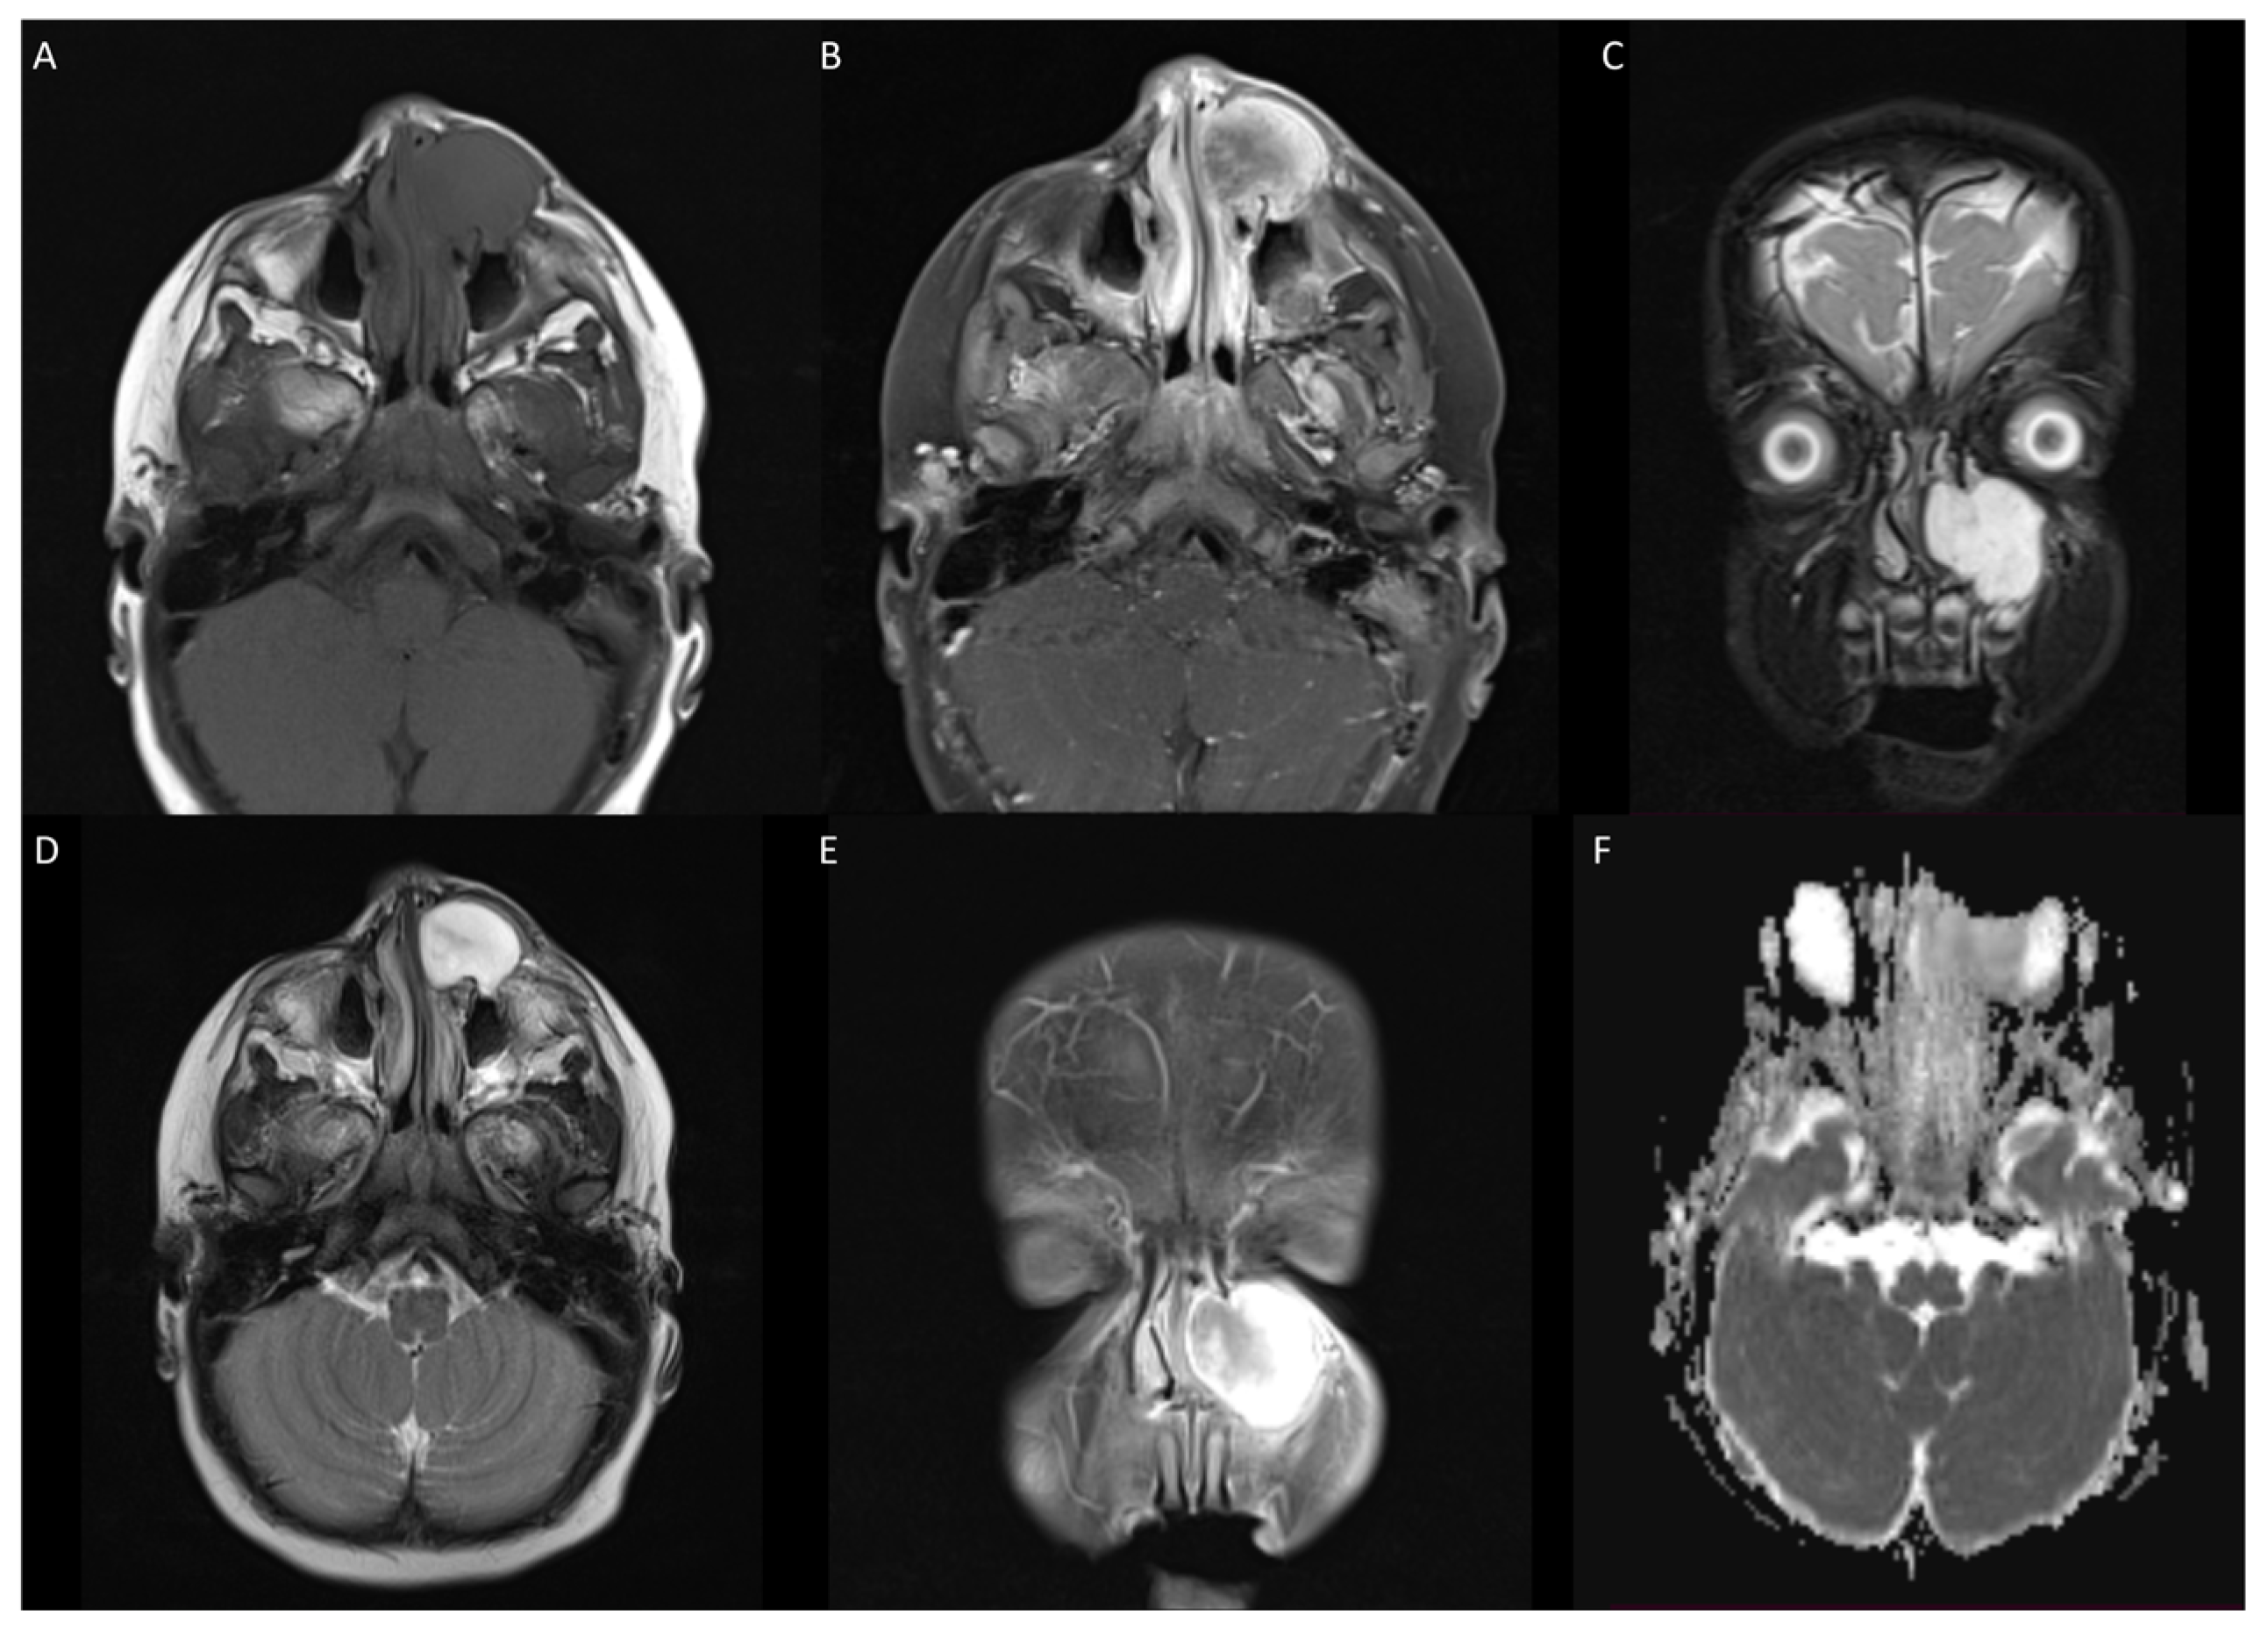

3.1. Case 1